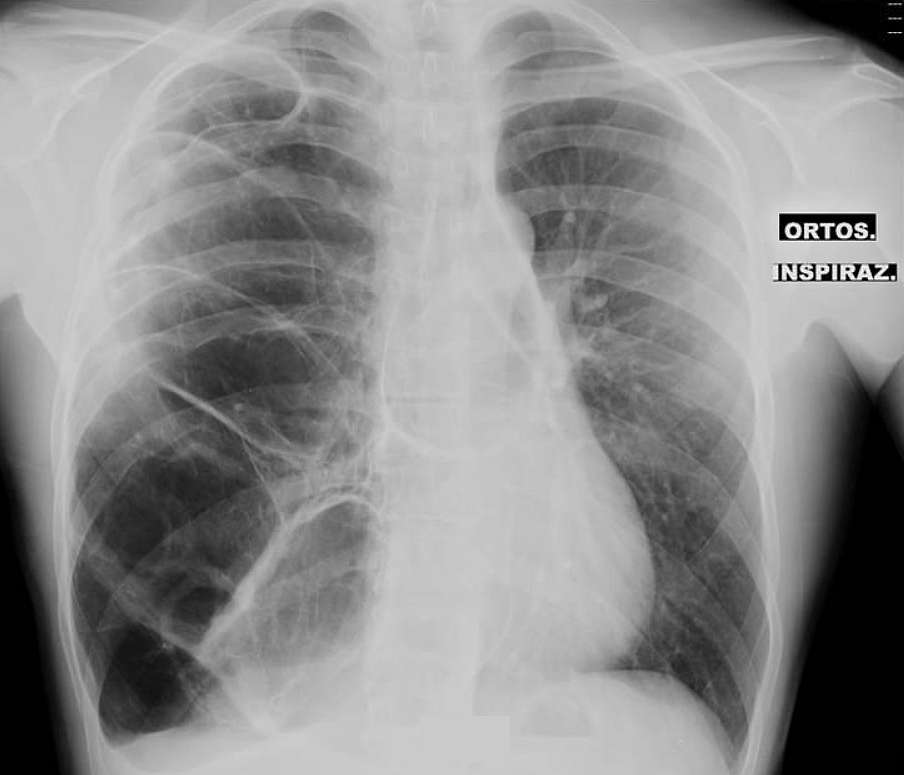

Patient with Right Subscapular Pain and Tachycardia Post category:Spot Diagnosis Post published:March 9, 2024 Share on Facebook Share on X (Twitter) Share on Pinterest Share on Email Share on Reddit A 21-year-old male patient was admitted to the Emergency Department for right subscapular pain and tachycardia suspicious for pneumothorax. Patient with Right Subscapular Pain and Tachycardia What could the diagnosis be ? FULL CASE AND ANSWER Share on Facebook Share on X (Twitter) Share on Pinterest Share on Email Share on Reddit Read more articles Previous PostGums Discoloration Next PostProgressive Fingertip and Toe Enlargement You Might Also Like Palpable, Ropelike Cord from the Left Medial Malleolus to the Groin July 7, 2021 Woman with Dermatomyositis and Subcutaneous Nodules on the Arms and Legs May 13, 2022 Patient with History of Esophageal Stenosis due to Chemical Burn April 14, 2022